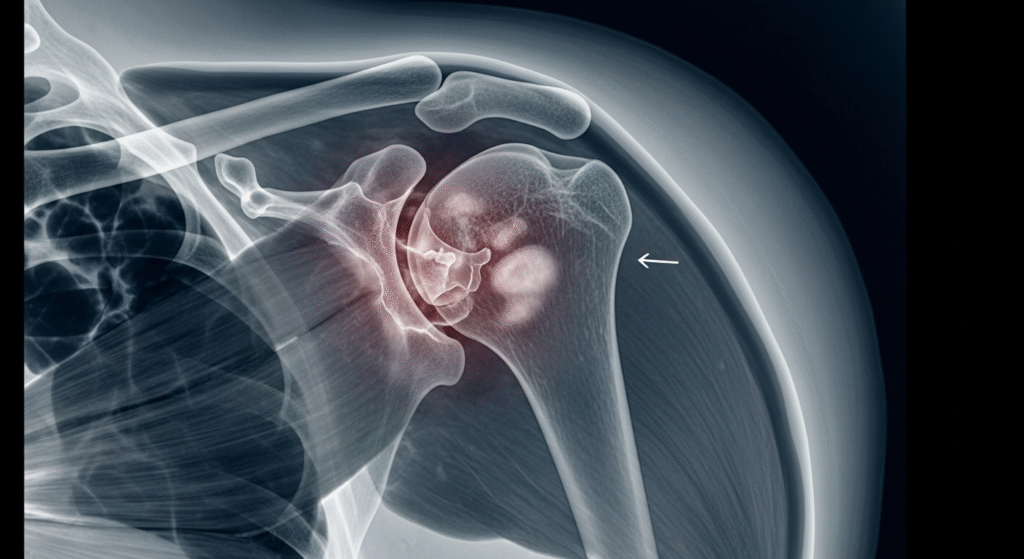

😱 Shocking Shoulder Infection Finally Treated — The Hidden Damage Beneath the Skin Revealed

At first glance, this shoulder injury looks like a minor skin problem. But medical experts warn that what appears on the surface is often just a small window into a much deeper infection developing underneath the skin.

The inflamed, green-centered lesion seen in this case is a strong indicator of a serious bacterial skin infection that has been growing over time without proper treatment.